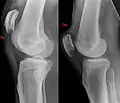

| An x-ray demonstrating quadriceps tendon rupture. Note the abnormal angle of the patella and soft-tissue swelling marked by the arrow. | |

A quadriceps tendon rupture is a tear of the tendon that runs from the quadriceps muscle to the top of the knee cap.[1]